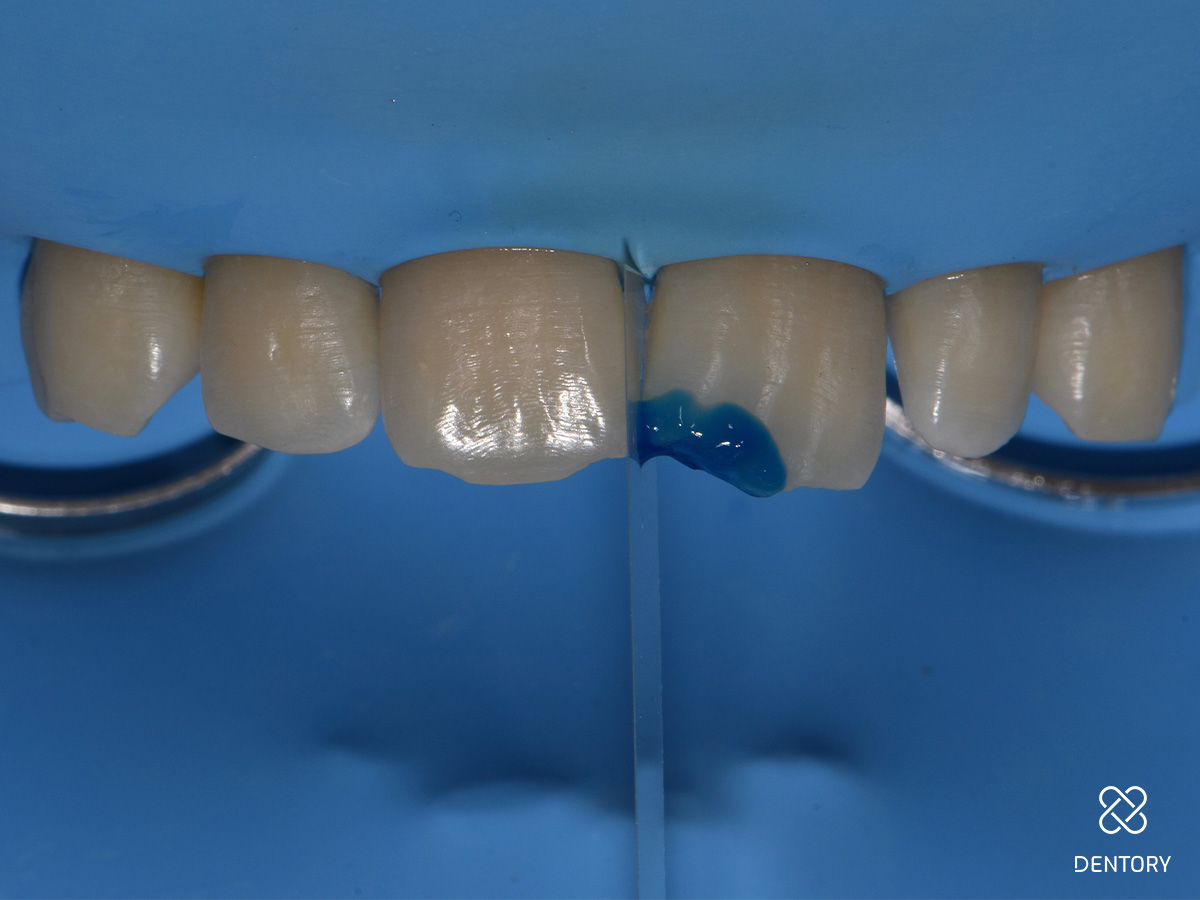

Abbildung 1

Farbbestimmung: Für die Farbauswahl werden Komposit-Proben direkt auf den Zahn platziert und ausgehärtet. In diesem Fall wurden A2 (o.r.) und Enamel Light (EL, u.r.) gewählt.